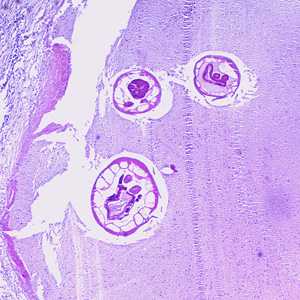

Oesophagostomum spp. in tissue specimens.

Figure A: Cross-section of an adult of Oesophagostomum sp. in a colon biopsy specimen from a patient from Africa, stained with H&E. Image taken at 40x magnification.

Figure B: Higher magnification (200x) of the specimen in Figure A. Note the large, platymyarian muscle cells (MU), intestine with brush border (IN), and paired reproductive tubes (RT).

Figure C: Higher-magnification (200x) of the specimen in Figure A. Note the large, platymyarian muscle cells (MU) and thick, muscled esophagus (ES).